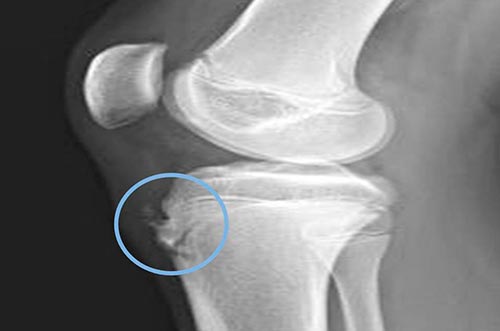

Рентгенологические признаки патологии неявные и неспецифические. Диагностика затруднена наличием большого количества вариантов оссификации апофиза, которая может протекать по-разному даже на конечностях одного человека.

При оценке рентгеновского снимка врач ориентирует на разницу в степени выбухания хряща и его величиной на полученном изображении. В результатах лабораторного исследования присутствуют неспецифические симптомы воспаления: увеличение СОЭ, умеренный лейкоцитоз, сдвиг формулы влево (увеличение процента молодых форм нейтрофилов в крови).

Болезнь Шляттера у подростков диагностируется на основании комплекса исследований: рентген, лабораторные анализы, анамнез, клинические проявления и жалобы.

| Рентгенография суставов | , | На рентгенограмме видны отек мягких тканей, утолщение хряща, покрывающего бугристость спереди, фрагментация бугристости. |